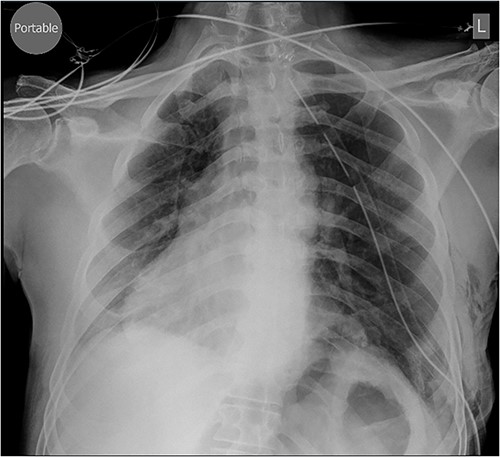

A 79-year-old male was referred by his general practitioner for consideration for repair of diaphragm eventration. The elevated left hemidiaphragm was noted on chest X-ray approximately a decade before. Referral was prompted by an episode of postprandial shortness of breath and a long-standing inability to belch. Medical history is significant for hypertension and tachyarrhythmia controlled on Flecainide. Clinical examination was remarkable for the presence of bowel sounds in the left chest at the level of the nipple, and apex beat on the right. Chest X-ray showed a markedly elevated left hemidiaphragm with dextrocardia (Fig. 1). Pulmonary function tests (PFT) showed small airway defect with normal lung volumes and diffusion capacity. Chest computed tomography showed no pathology other than the eventration.